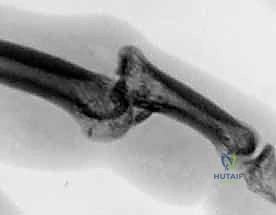

3. التثبيت الخارجي الديناميكي (Dynamic External Fixation)

تعتبر هذه التقنية ثورة في علاج الكسور المفتتة بشدة (كسور بيلون) حيث يكون العظم مهشماً كعجلة القيادة المكسورة.

* كيف تعمل؟ بدلاً من فتح المفصل، يقوم الدكتور هطيف بإدخال أسلاك معدنية دقيقة عبر الجلد إلى العظام السليمة فوق وتحت المفصل المصاب. يتم توصيل هذه الأسلاك بإطار خارجي مرن (مثل إطار سوزوكي Suzuki Frame).

* الميزة: يعتمد هذا الإطار على مبدأ "الشد الرباطي" (Ligamentotaxis). فهو يسحب المفصل بعيداً عن بعضه، مما يسمح للقطع العظمية المفتتة بالاصطفاف في مكانها الطبيعي بفضل الشد المعاكس للأربطة المحيطة، وفي نفس الوقت يسمح للمريض بثني ومد